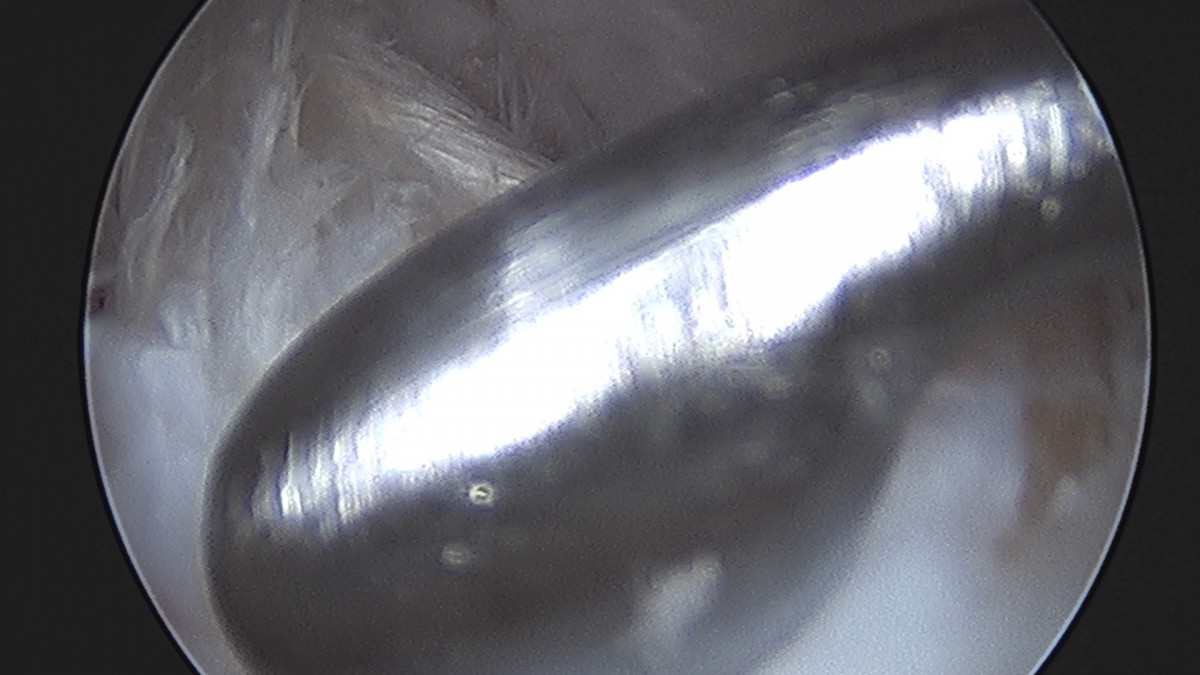

이재상원장님 무릎 반월상 연골판 절제술 박대O 환자

dae765e4d9ac96aee867c9d6292d8784_1758005044_0264.jpg